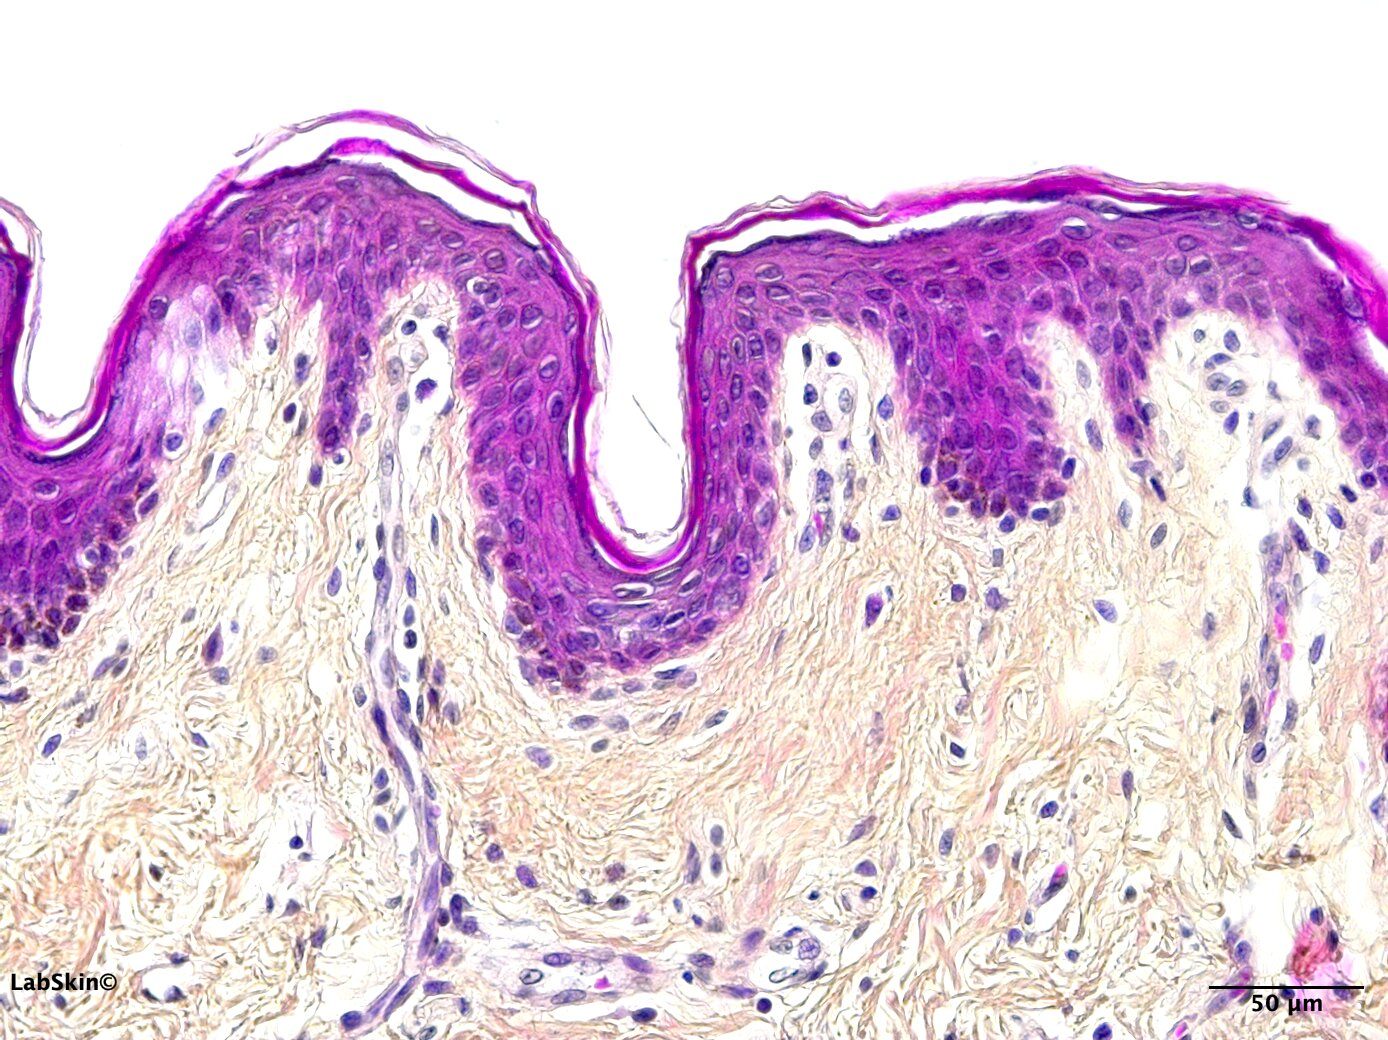

HEMATOXYLIN PHLOXIN SAFFRON

NORMAL HUMAN SKIN